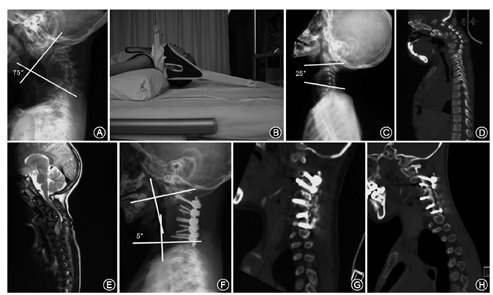

1例患者C3-6椎体发育不良,平衡悬吊牵引1周后预矫正率超过50%,单纯颈椎后路C2-7组织松解,关节突关节截骨后行C2-7椎弓根钉固定,植骨融合术。患者全身麻醉后俯卧位,头部用Mayfield头架固定。清除瘢痕和纤维化的棘间韧带及关节囊组织,行关节突截骨。置入椎弓根螺钉,安放预弯的连接棒。台下的助手抬起Mayfield头架使颈部适度后仰,安放固定螺钉,借助连接棒的弧度达到矫形效果。

1例患者椎体发育不良,仰伸位X线片示复位超过50%,未予牵引一期行颈椎后路C1-7侧块钉棒固定,后凸矫形植骨融合术。

1例患者C3-5椎体发育不良,平衡悬吊牵引1周后预矫正率超过50%,颈椎前路C2-5椎间盘切除,C2/3 Cage植入,C4椎体次全切除,3D打印人工椎体植入,钛板内固定术。术中行标准的椎间盘切除,注意双侧颈长肌的松解,移除瘢痕挛缩组织,逐级撑开,植入带有自体骨的Cage及3D打印假体,预弯钛板固定,后凸矫形融合。

1例患者C2-4椎间盘突出,C2棘突过长影响后伸。颅骨牵引1周后预矫正率未超过50%,后路C2-4软组织松解,切除过长C2棘突,一期前路C2-4椎间盘切除,Cage植骨融合,钛板内固定术。

1例患者C3-6椎体发育不良,颅骨牵引1周后预矫正率超过50%,行颈椎前路C2-7椎间盘切除,C3-6椎体切除,颈长肌切断松解。3周后颈椎后路C2-7小关节松解侧块固定融合术,颈前路C2-7钛网植入,钛板内固定术。先行后路手术的病例后路截骨完成后在助手的帮助下改变患者体位,轴向翻身,取仰卧重新消毒铺巾,摆体位时注意不必过分后伸,注意脊髓监测的MEP变化。

患者术后进行3个月、6个月、1年及2年随访,最长随访时间7年,8例患者随访6~84个月,平均36个月。随访时行X线及CT、MRI检查,末次随访时显示均获得骨性融合。8例患者术前后凸区域中立位Cobb角为45°~92°,平均为67°±18°。4例诊断为椎体发育不良患者中有3例术前均行牵引预矫形,预矫形率超过50%,另外1例仰伸位X线示后凸矫形率超过50%。未进行牵引预矫形,一期后路手术。1例诊断为C3-6椎间盘突出,C2棘突过长,颈椎后凸畸形患者,仰伸位X线矫形率未达到50%,牵引后由于C2棘突过长影响后伸无进一步复位遂行颈后路软组织松解C2过长棘突切除,然后前路手术。另外3例诊断为颈椎分割不全,半椎体畸形及椎体先天融合患者,仰伸位X线无明显复位,均一期前路,后路或前后路联合手术。术后出院前中立位Cobb角为0°~23°,平均为8°±8°,较术前显著改善(t=8.471,P<0.05)。末次随访中立位Cobb角为0°~26°,平均为12°±6°,术后矫形率为66%~100%,平均为87%±13%。JOA评分由术前(11.1±2.7)分改善至术后(14.0±1.5)分(t=-2.656,P<0.05)(表1)。